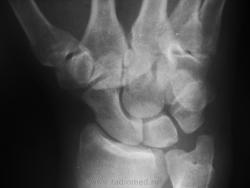

что можно сказать, случается и такое, а по поводу повреждения во2-3 пястно-запястном суставах нужна боковая проекция.

В правильной прямой, боковой и тыльной косой проекциях. (Снимки при поступлении выполнялись на выходных, много бинтов, и обе первичные укладки неправильные косые.)

А так вроде и нормально в запястье... Или ошибаюсь? Репозицию выполняли только с пальцем, шов сухожилия разгибателя.

сейчас вроде все нормально, а на первичных снимках вывих скорее всего был, возможно при проведении манипуляций обезболивание, ПХО самапроизвольно вправилось.

Хотя, будь первичный снимок в классической прямой проекции, может, и вопросов бы не возникло...